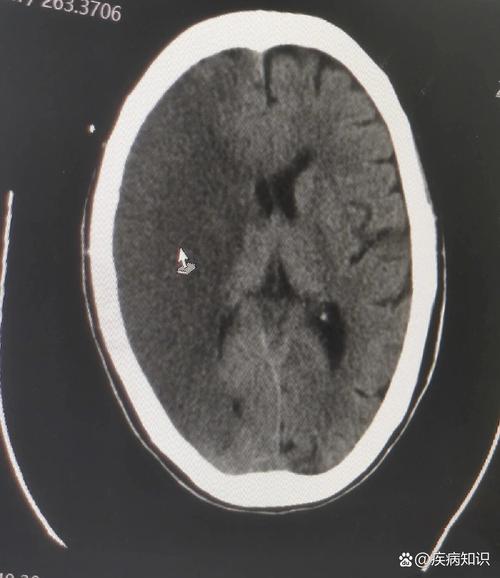

先看“有没有”——排除最紧急的情况(脑出血)

这是CT看急性脑梗的首要任务,医生必须在几分钟内判断患者是脑梗(缺血性)还是脑出血(出血性),因为这两种病的治疗方案完全相反,甚至相反!

- 看哪里: 整个大脑的实质部分。

- 看什么: 有没有异常的白色高密度影?

- 没有白色高密度影: 强烈提示是缺血性脑梗(脑梗塞),因为新鲜的脑出血在CT上会非常显眼,像一个白色的“血块”。

- 有白色高密度影: 那就不是脑梗,而是脑出血,需要立刻进行止血等治疗。

【关键点】:对于急性脑梗(发病6小时内),普通的平扫CT可能完全正常!这是CT诊断脑梗最大的局限性,只有在发病24-48小时后,坏死的脑组织才会因为水分增多而显示出低密度(黑色)区域。